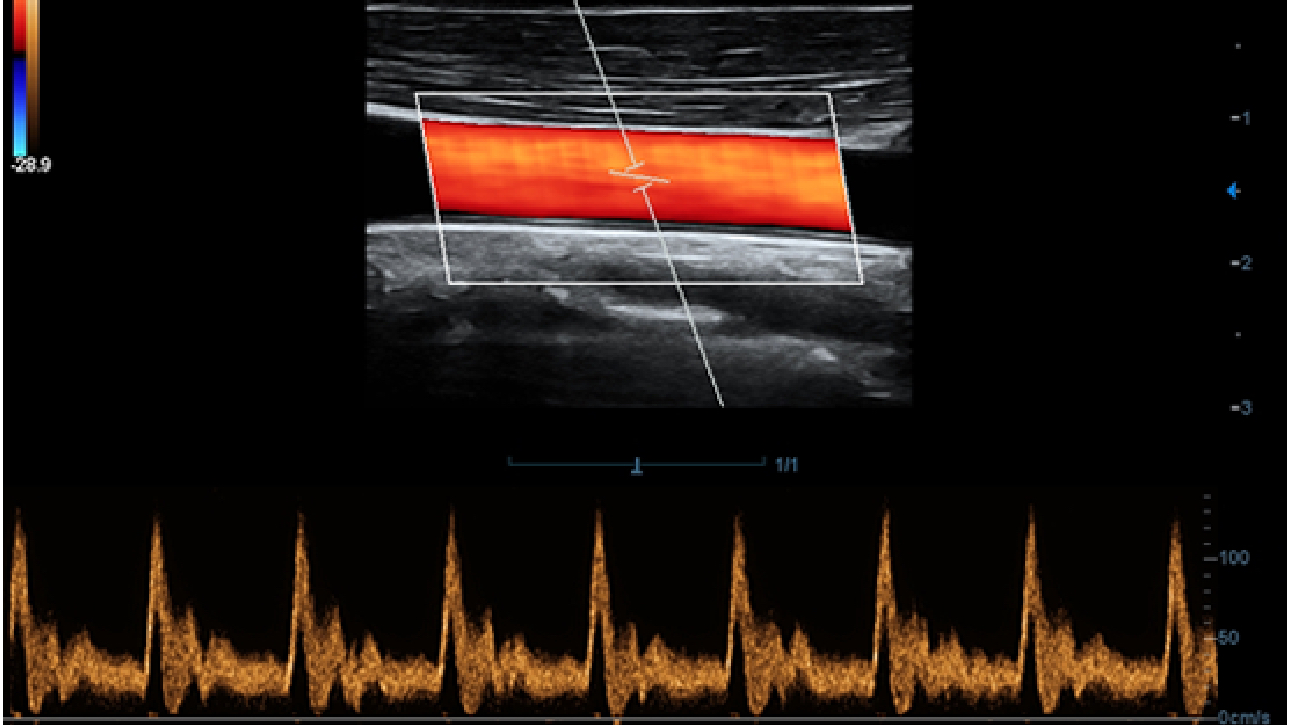

X-Insight es la soluci├│n intuitiva para una mejor visualizaci├│n.

La nueva soluci├│n de Mindray es una excelente transformaci├│n desde la continua comprensi├│n de las necesidades cl├Łnicas del usuario, combinada con la evoluci├│n de la tecnolog├Ła de los ultrasonidos m├Īs puntera. Repleto de vitalidad, con el ├║nico objetivo de visualizar el futuro y evitar los l├Łmites, el ec├│grafo DC-60Exp con X-Insight est├Ī constantemente mejorando con una escalabilidad aumentada. Como un socio personal, el equipo de ultrasonidos DC-60 Exp con X-Insight se centra en lo que verdaderamente importa, ayudando al usuario a administrar su pr├Īctica cl├Łnica con facilidad y seguridad.

Bas├Īndose en una profunda comprensi├│n de las necesidades del usuario, el sistema de ultrasonidos DC-60 Exp con X-Insight est├Ī dise?ado para ofrecer una alta eficiencia con im├Īgenes de precisi├│n, la cual se ve potenciada por una claridad inmediata, una inteligencia excepcional y benefici├Īndose de una c├│moda experiencia.